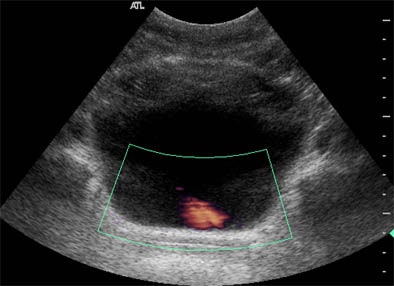

![]() |

| Remotely guided Doppler ultrasound of the left ureter shows urine flow (pink) into the bladder. |